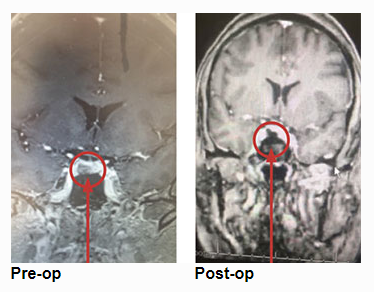

This is a 46-year-old woman who presented with a 9 mm right-sided pituitary adenoma with a recent diagnosis of Cushing’s Disease. For two years she noticed some swelling of her body. The swelling was much more noticeable recently. She had pronounced swelling of her face, body, and legs. She was also recently diagnosed with hypertension and diabetes. She also had some recent impairment of her memory and thought processes. Her endocrine testing was consistent with Cushing’s Disease, that is, a pituitary source of her high systemic cortisol levels.

She underwent endoscopic transsphenoidal removal of the pituitary tumor, performed by Dr. Michael Brisman. Postoperative imaging showed the tumor was removed completely. Postoperative lab tests showed very low serum cortisol levels, consistent with a successful operation. She was placed on replacement hydrocortisone. She was feeling much beer, and her hypertension and diabetes were much improved. It is expected that she is cured of her Cushing’s Disease. She will undergo periodic follow-up imaging and lab tests.